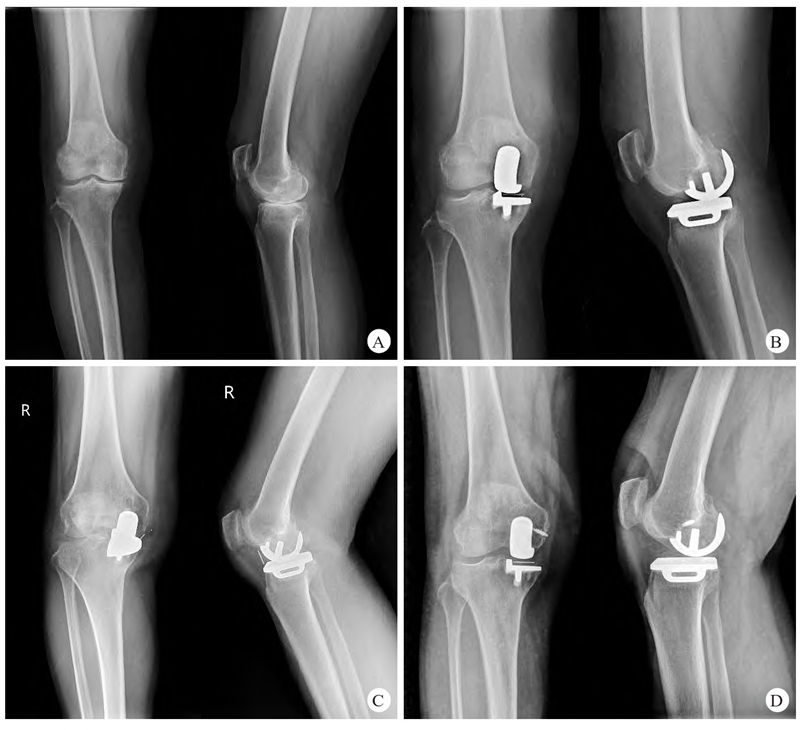

典型病例:图1 患者,女,64岁,右膝内侧间室骨关节炎,行活动平台UKA

A.术前右膝正、侧位X线片显示膝关节内侧间隙变窄;B.术后1周右膝正、侧位片X线片显示假体位置良好;C.术后6个月下蹲站立后出现右膝关节疼痛,右膝正、侧位X线片提示衬垫向前方脱出;D.更换新的原厚度衬垫+内侧副韧带锚钉固定术后1个月,右膝正、侧位X线片显示衬垫位置良好,假体对位恢复正常